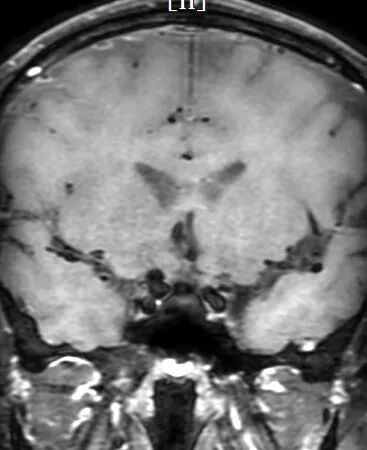

术前影像学检查:高分辨率MRI未见明显强化,CTA显示右侧颈内动脉眼动脉段动脉瘤。

动脉长鞘怎么置入深谋远路 | 千人皆翘首,万唤今始来——国内首款7F长鞘在血流导向密网支架联合弹簧圈栓塞治疗动脉瘤的首次应用_https://www.jmylbn.com_新闻资讯_第19张

高分辨率MRI未见明显强化

CTA显示右侧颈内动脉眼动脉段动脉瘤